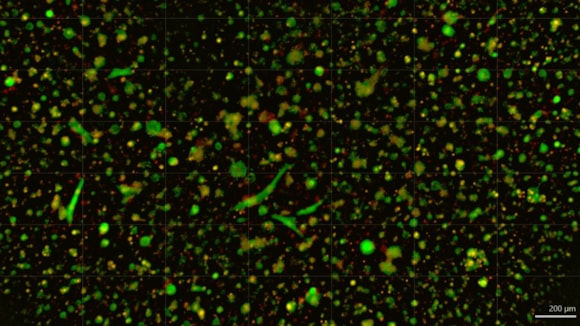

ChristianaCare Launches Organoid Core to Personalize Cancer Treatment: carboplatin treatment 4 zoomed 2

Tumor organoids are tiny, three-dimensional cultures grown from a patient’s tumor tissue. They preserve the genetic and molecular traits of the original tumor, making them far more accurate than traditional cell lines.